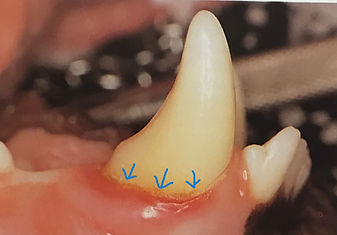

Examples of dental disease and stages can be seen in the pictures below.​​